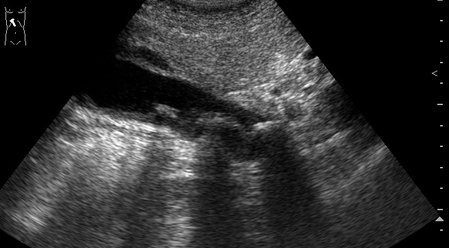

Пожилой мужчина, обратился в приемный покой БСМП с жалобами на периодические тупые боли в эпигастрии и правом подреберье. Год назад были сильные боли в правом подреберье, лечился самостоятельно дома.

Я бы поставил на основании выше показанного и изложенного - Холецистолитиаз, обострение. :)

слизистая в просвете желчного пузыря, что говорит о некрозе его стенки ... острый калькулезный холецистит, с перфорацией.. :ugeek:

при поперечном сканировании на втором ролике, скопление свободной жидкости в паренхиме печени :twisted:

Острый калькулезный гангренозный холецистит.

Особенность этого случая в том, что создается впечатление о перфорации стенки пузыря в области дна и наличии скопления желчи в области ложа пузыря.

В действительности перфорации стенки пузыря не было.